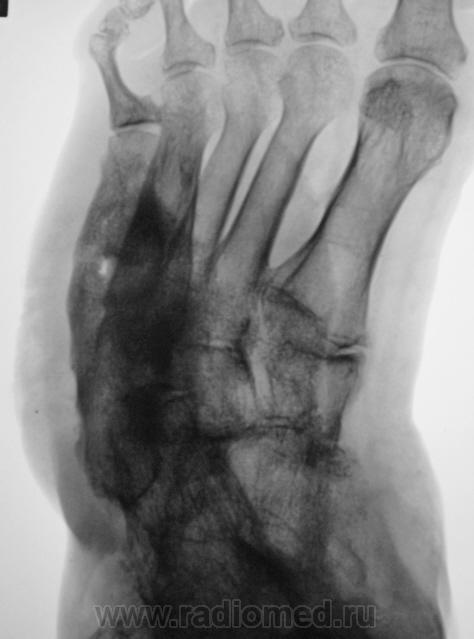

Пациентка направлена на рентгенографию стоп.

Направительный диагноз - "Диабетическая ангиопатия".

Хирург, увидев только одну стопу - правую, левая, еще была в работе, ответственно заявил - "остеогенная саркома"...

Системное поражение, возможно как следствие диабетической ангиопатии;слева V плюсневая кость с прерывистым контуром ( возможно остеонекроз на фоне ангиопатии). Не видел подобного ранее.

Картинка вобрала в себя все, что клинически называют "диабетическая стопа". Здесь последствия и ангиопатии, и нейропатии, и присоединившейся инфекции. По-моему, имеется и трофическая язва. Прямо студенческий случай. Хотя, я тоже ранее таких стоп не видел.

Было бы односторонне поражение, подумал бы про мелореостоз.

Хронология с 1997 года.